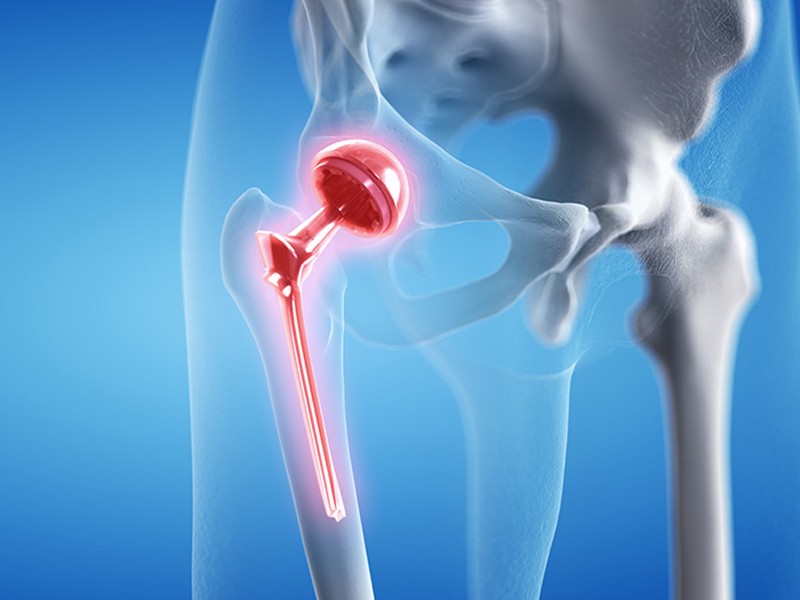

Revision Hip Replacement

A hip replacement is a life-changing procedure, but sometimes, due to wear and tear, infection, implant loosening, or other complications, the initial hip replacement may fail or cause discomfort. This is where Revision Hip Replacement becomes necessary. Our team of highly skilled orthopedic surgeons specializes in performing complex revision hip surgeries to restore function, reduce pain, and improve quality of life.

Revision Hip Replacement is a surgical procedure performed to replace or repair a previously implanted artificial hip joint that is damaged, worn out, or causing pain. Unlike primary hip replacement, revision surgery is more complex as it requires careful removal of the old implant and reconstruction of the joint.